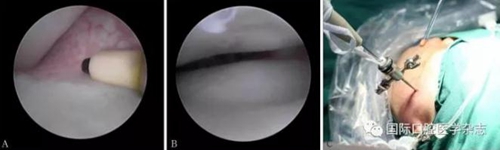

(1)顳下頜關節(jié)鏡微創(chuàng)治療。使用關節(jié)鏡治療的適應證:顳下頜關節(jié)紊亂病,保守治療效果不佳,病情較重者(圖17)。2)顳下頜關節(jié)盤復位錨固術(圖18)。使用顳下頜關節(jié)盤復位錨固術治療的適應證:顳下頜關節(jié)紊亂病,保守治療無效,關節(jié)鏡手術效果不佳者。

A:射頻刀松解黏連帶;B:復位后的關節(jié)盤;C:關節(jié)鏡術中。

圖 17 關節(jié)鏡手術